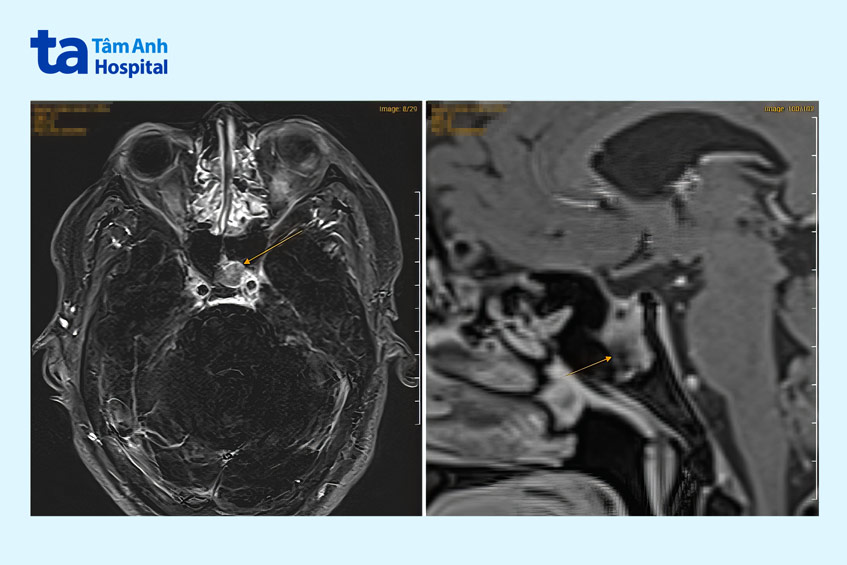

Anh Quang được chuyển đến khoa Nội tiết – Đái tháo đường, ThS.BS Trần Nguyễn Quỳnh Trâm, Phó khoa, chỉ định chụp cộng hưởng từ (MRI). Kết quả ghi nhận người bệnh có tổn thương tuyến yên lệch trái gây khuyết thành dưới hố yên, lồi vào xoang bướm trái, kích thước khối u lớn 10x9x14 mm. Đây là nguyên nhân khiến người bệnh suy sinh dục thứ phát, vô sinh.